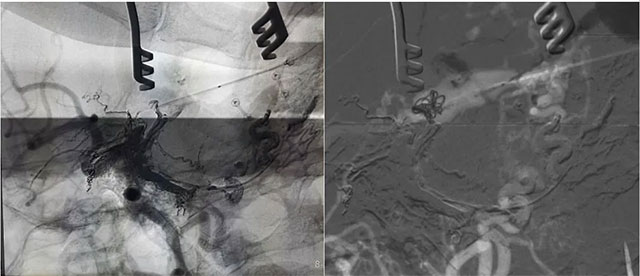

▲ 再次造影确认位置后,填入 HELIX 6/20弹簧圈

▲ 微导管造影确认后,注入 Onyx 18胶 5ml

经左侧股动脉以单弯造影管超选至左侧颈总动脉造影明确静脉穿刺点入路,予以穿刺针穿刺成功后造影明确在位,随后 Echelon 10微导管到位横窦,填入一枚弹簧圈做塞子,造影明确位置后,缓慢注入 Onxy18胶 5毫升,铸胶弥散良好,通过静脉逆向弥散至部分供血动脉内。复查造影,见瘘口完全被栓塞,引流静脉消失,手术成功。